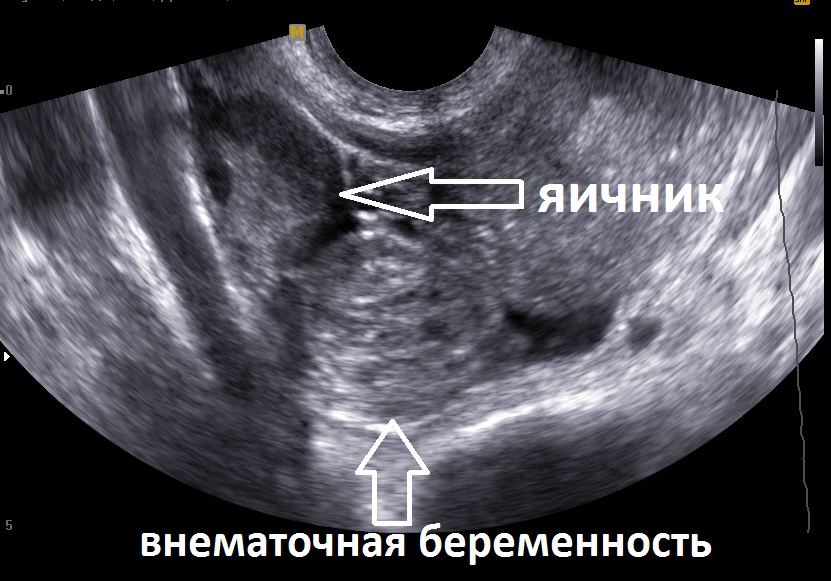

- УЗИ;

С помощью интравагинального УЗИ можно поставить диагноз уже на второй неделе. Но происходит такое редко. Так как женщины, обычно, обращаются к врачам куда позже.

Диагностика внематочной беременности обычно включает в себя гинекологический осмотр, анализы крови на уровень ХГЧ (хорионического гонадотропина человека) и ультразвуковое исследование. УЗИ помогает определить местоположение беременности и исключить нормальную маточную беременность.